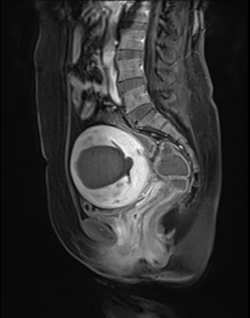

ÀڱñÙÁ¾°ú Àڱü±±ÙÁõÀº ´Ù¸£´Ù Àڱü±±ÙÁõÀº ¸¹ÀÌ ¾Ë·ÁÁ® ÀÖ´Â Àڱà Áúȯµé¿¡ ºñ±³Àû »ý¼ÒÇÑ ÁúȯÀÌ´Ù. ÀϹÝÀûÀ¸·Î Àڱÿ¡ ÀÌ»óÀ» ´À³¢¸é ÀڱñÙÁ¾À¸·Î ¿ÀÇØÇϱ⠽¬¿îµ¥ ÀڱñÙÁ¾Àº Àڱÿ¡ ȤÀÌ »ý°Ü ¸íÈ®ÇÏ°Ô º¸ÀÌ´Â °ÍÀ̰í, Àڱü±±ÙÁõÀº Àڱú®ÀÌ µÎ²¨¿öÁö´Â ÁúȯÀ¸·Î ¸í¹éÈ÷ ´Ù¸£´Ù. µÎ Áúȯ ¸ðµÎ ÃÊÀ½ÆÄ·Î Áø´ÜµÇ´Âµ¥ Àڱü±±ÙÁõÀÇ °æ¿ì ÀÚ±ÃÀÌ ºñ´ëĪÀûÀ¸·Î ÄÑÁ® ÀÖÁö¸¸ ¶Ñ·ÇÇÑ È¤Àº º¸ÀÌÁö ¾Ê´Â´Ù. ÃÊÀ½ÆÄ·Î Á¤È®È÷ º´º¯ÀÌ º¸ÀÌÁö ¾Ê°Å³ª È®ÀÎÀÌ ¾î·Á¿î °æ¿ì¿¡´Â MRI¸¦ ÅëÇØ Á¤¹ÐÇÑ Áø´ÜÀÌ °¡´ÉÇÏ´Ù.